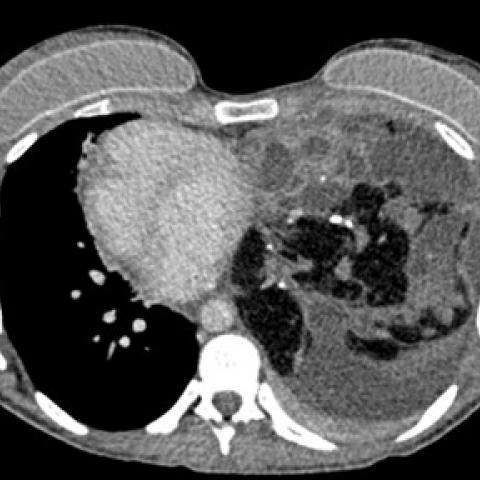

随后进行胸部对比增强CT(计算机断层扫描),结果显示非常大的团块占据左肺大部分,并且左上叶保留。团块由软组织组成,具有肉眼可见的脂肪灶,液性变薄的囊性区和多个钙化灶。CT进一步证实了纵隔移位的程度和左胸腔存在积液。纵隔淋巴结无明显肿大,无骨性病变,无肺扩张。组织学证实有大量成熟的肺内畸胎瘤。

图2 轴向CT显示,左肺内存在大量软组织团块,包括肉眼可见的脂肪、液性变薄的囊性区和多个钙化灶。少量胸腔积液,纵膈移位。